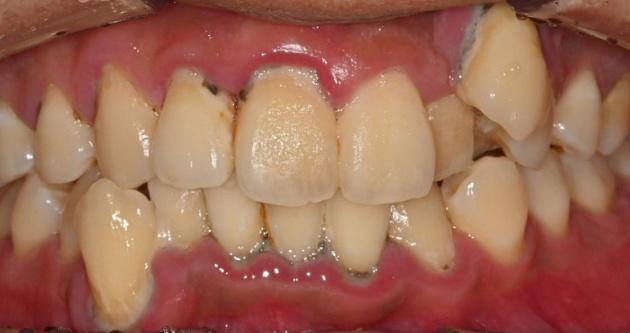

실제 사례 Before & After

바른선택치과의원은 결과로 증명합니다. 기능과 심미 모두 찾은 바른선택치과의원 실제 환자 케이스를 확인해보세요.

before Before

after After

치료 시작 전 촬영 2025.02.18 | 치료 완료 후 촬영 2025.02.28

※ 바른선택치과의원은 의료법을 준수하며 위 케이스는 실제 내원 환자분의 동의하에 공개된 사진과 동일한 환자분께 같은 조건에서 촬영한 사진을 활용했습니다.

개인에 따라 진료 및 치료 방법이 다르게 적용할 수 있으며, 효과와 부작용이 개인마다 다르게 나타날 수 있는 점을 안내해 드리며, 진료 전 전문의료진과 충분한 상담을 권해드립니다.